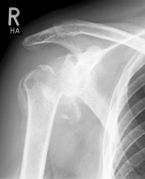

Abbildung11(2)Abbildung11

Fracture prostheses for complicated humeral head fractures

left: X-ray of a humeral head fracture before treatment with a fracture prosthesis.

right: X-ray of a humeral head fracture after treatment with a fracture prosthesis